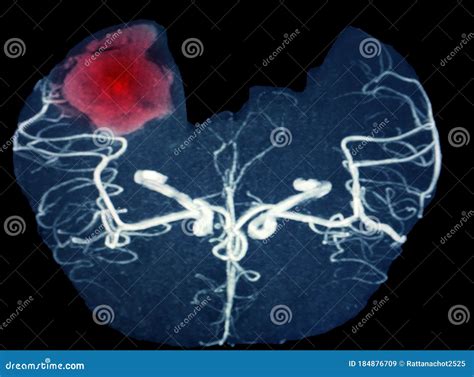

Magnetic Resonance Venography (MRV) is a sophisticated medical imaging technique that uses magnetic fields and radio waves to generate detailed images of the cerebral veins. Unlike a standard MRI, which primarily looks at the brain tissue itself, an MRV is specifically designed to assess blood flow and identify potential abnormalities within the venous system.

Doctors frequently use this scan to detect issues such as cerebral venous thrombosis (blood clots in the brain's veins), narrowing of the veins (stenosis), or other vascular anomalies that might be affecting cerebral circulation.